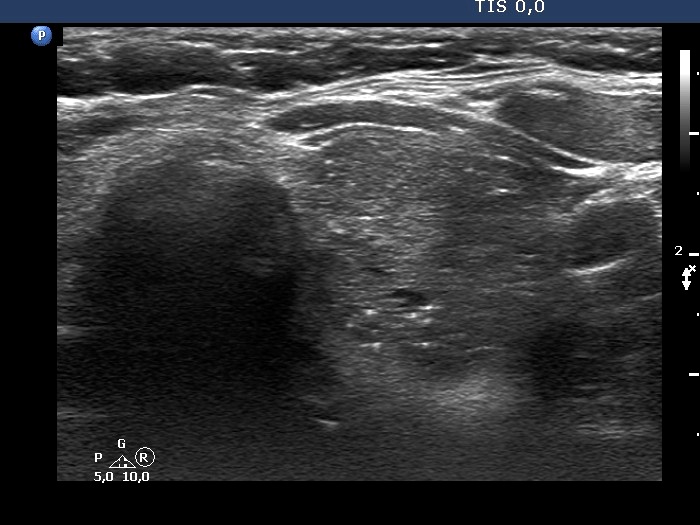

Second examination 7 years later (second and third rows of images):

Clinical presentation: The patient remained euthyroid in the previous years an had no complaints.

Palpation: unchanged.

Result of blood test: TSH 0.34 mIU/L, FT4 14.2 pM/L

Ultrasonography. The presentation remained unchanged. Using a better ultrasound device, it turned out that the echogenic granules are related to ventral cystic areas. Therefore, these are not microcalcifications, but figures caused by back wall cystic enhancement.Suggestion: yearly TSH determination, ultrasound in 4 years.